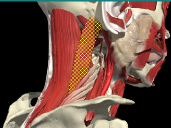

LOCALIZATION OF MUSCLES IN DEEPER LAYERS

Layer 1

Layer 2

Layer 3

Splenius Capitis

Semispinalis Capitis

Longissimus Capitus

Semispinalis Cervicis

ACCURACY OF LOCALIZATION – DEEPER LAYERS